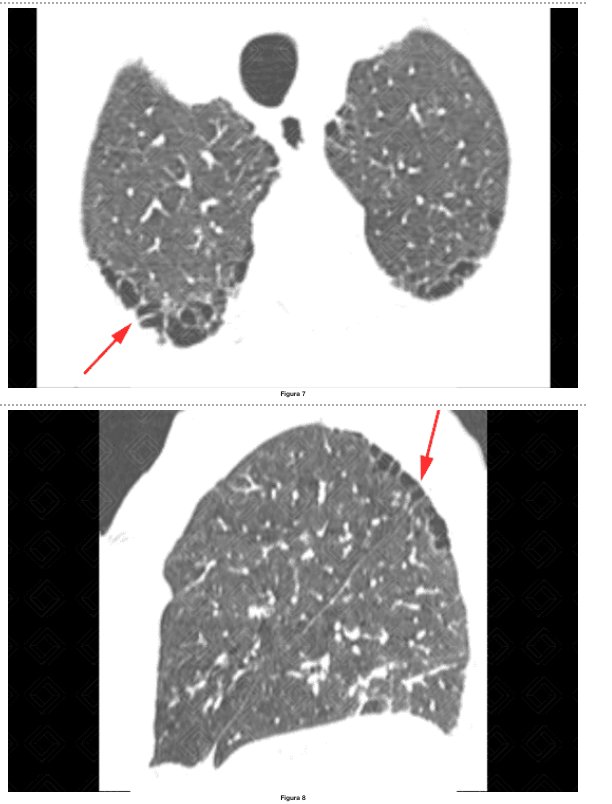

Quais são os achados na TC comuns em pacientes com DPOC?

TC, pois apresenta maior nitidez e exatidão para a detecção de alterações relacionadas à DPOC (ex: enfisema) e auxilia no screening de câncer de pulmão uma vez que a maioria dos pacientes com risco para DPOC são tabagistas.